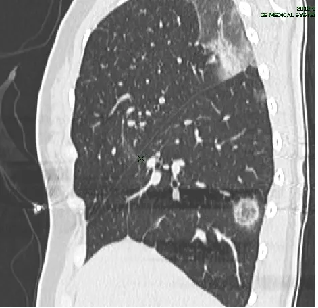

程大叔来到某医院,医生给他做了一个胸部CT,结果却让他大吃一惊,CT提示:双肺多发结节,性质待定,考虑到程大叔 50多岁,长期抽烟,这可是妥妥的肿瘤高危人群啊,现在又是咳嗽又是胸痛的,难道真的是肺癌?

程大叔的胸部CT

程大叔的女儿立即将他带到自贡市第四人民医院呼吸与危重症医学科,接诊的医生阅读胸部CT检查单后并分析,考虑良性的炎性病灶可能性更大,以最快的速度安排了肺穿刺活检